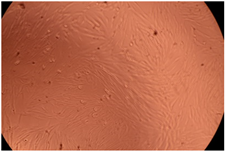

| Sample | Micrographs | ||

|---|---|---|---|

| 24 h | 48 h | ||

| Control |  |  | |

| F127 | 10 µg/mL |  |  |

| 50 µg/mL |  |  | |

| 100 µg/mL |  |  | |

| 200 µg/mL |  |  | |

| F127/PA = 10/1 (g/g) | 10 µg/mL |  |  |

| 50 µg/mL |  |  | |

| 100 µg/mL |  |  | |

| 200 µg/mL |  |  | |